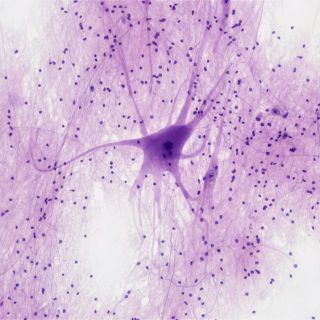

Estudiar el alzhéimer sin necesidad de biopsias cerebrales es clave y, ahora, un equipo científico ha diseñado un método para escudriñar en el laboratorio, células del cerebro envejecidas que reproducen 'con exactitud' las características de la enfermedad; para ello transformaron células de la piel de pacientes en neuronas.

Esta técnica, que transforma directamente en neuronas, células de piel de pacientes vivos obtenidas con facilidad, permite estudiar los efectos del alzhéimer en el cerebro sin el riesgo de una biopsia cerebral, detalla un comunicado de la Universidad de Washington.

Tras transformar células cutáneas en células cerebrales, los investigadores descubrieron que las nuevas neuronas pueden crecer en una fina película de gel o autoensamblarse en pequeños grupos, llamados esferoides, que imitan el entorno tridimensional del cerebro.